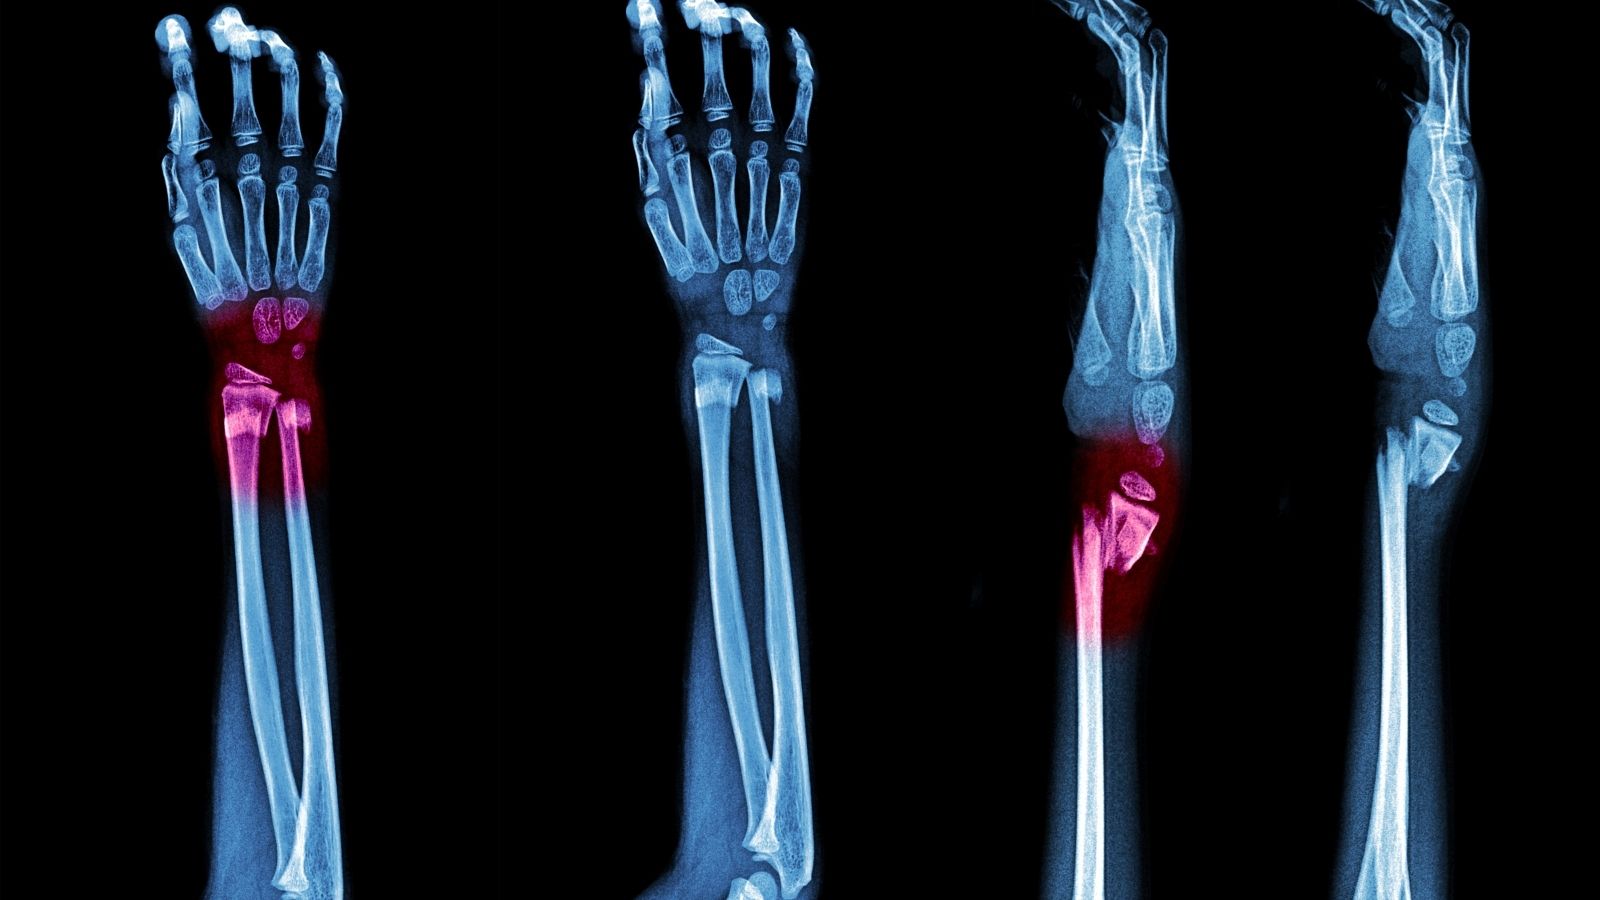

Doktora Gittiğinizde Baldır Kemiği Kırığı Tanısı Nasıl Konulur?

Muayenehaneye girdiğinizde ilk yaptığımız işlem detaylı bir fizik muayenedir. Yaralanmanın nasıl olduğunu anlatmanız, bize kırığın tipi hakkında önemli ipuçları verir. Elimizle yaptığımız muayenede, ağrının hangi noktada olduğunu (kemik üzerinde mi yoksa bağlar üzerinde mi) tespit etmeye çalışırız. Özellikle diz altına yakın bölgeleri de kontrol ederiz, çünkü bazen ayak bileği burkulmalarında enerjinin iletilmesi sonucu fibulanın dize yakın üst ucu da kırılabilir (Maisonneuve kırığı).

Fizik muayene bize şüpheyi gösterir ancak kesin tanı için radyolojik görüntüleme şarttır. Standart olarak istediğimiz tetkikler şunlardır:

- Ön-arka röntgen

- Yan röntgen

- Mortis grafisi

Özellikle “Mortis grafisi” bizim için çok değerlidir. Bu filmde ayak bileği yaklaşık 15 derece içe döndürülerek çekim yapılır. Bu sayede fibula ile kaval kemiği arasındaki eklem aralığını ve talus kemiğinin yuva içindeki pozisyonunu net bir şekilde görebiliriz.

Ancak bazen standart röntgenler her şeyi göstermez. Kırık hattı çok ince olabilir veya kemikler yerinde duruyor gibi görünse de bağlar kopmuş olabilir. Bu durumda “stres grafileri” devreye girer. Stres grafisinde, hekim ayak bileğini belli manevralarla zorlayarak film çektirir. Eğer bağlar kopuksa, bu zorlama sırasında eklem aralığı anormal şekilde açılır ve instabilite (gevşeklik) kendini belli eder.

Daha karmaşık kırıklarda, eklem yüzeyinin ne kadar hasar gördüğünü anlamak veya cerrahi planlama yapmak için Bilgisayarlı Tomografi (BT) isteriz. BT, kemiği üç boyutlu olarak dilimler halinde görmemizi sağlar. Kırık parçalarının ne kadar ayrıştığını, dönme olup olmadığını ve özellikle iki kemik arasındaki bağın (sindesmoz) durumunu en net BT ile ölçebiliriz.